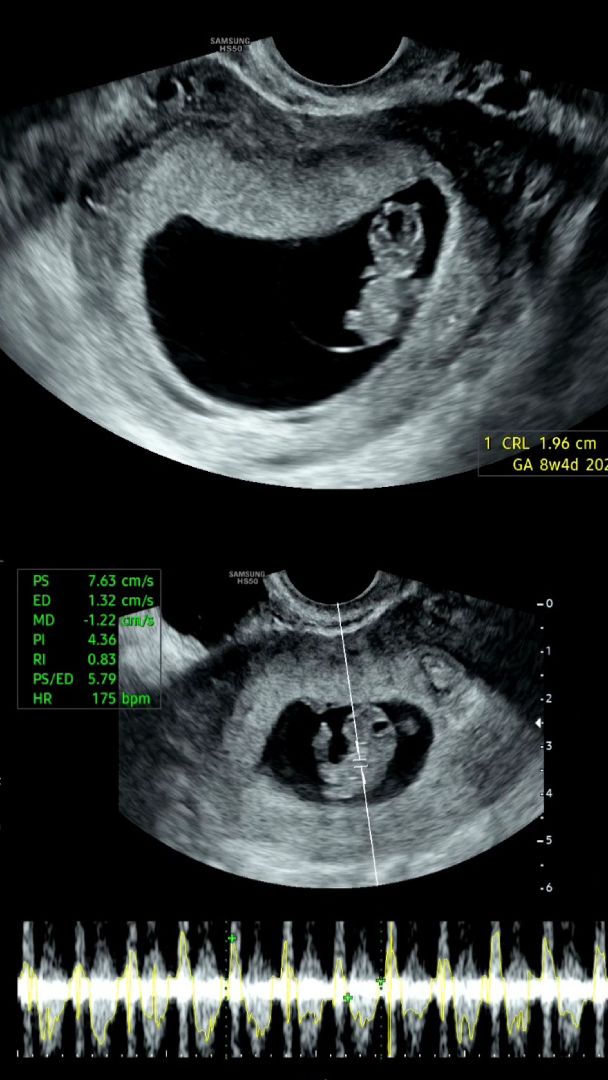

8주4일 초음파 봤어요~

8주차에 초음파 보신분들~ 아이 크기나 심장박동수 공유 가능하실까요~ 벌써 젤리곰이라니ㅠㅠ 심박수 175에 1.96cm정도면 잘크는걸까요?

예정일 6/8로 8주차 3일 1.96cm 180bpm이에요!